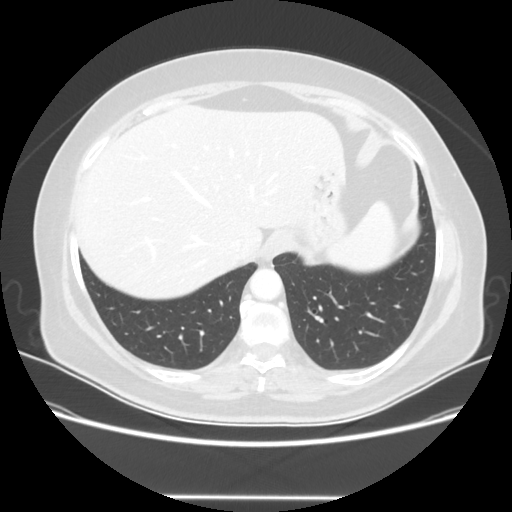

Reconstructed NATIVE CT scan (cycle consistency)

No window - Raw intensity values

Lung window (WL -600, WW 1500 β†’ Low βˆ’1350, High +150)

Mediastinum window (WL 40, WW 400 β†’ Low βˆ’160, High +240)